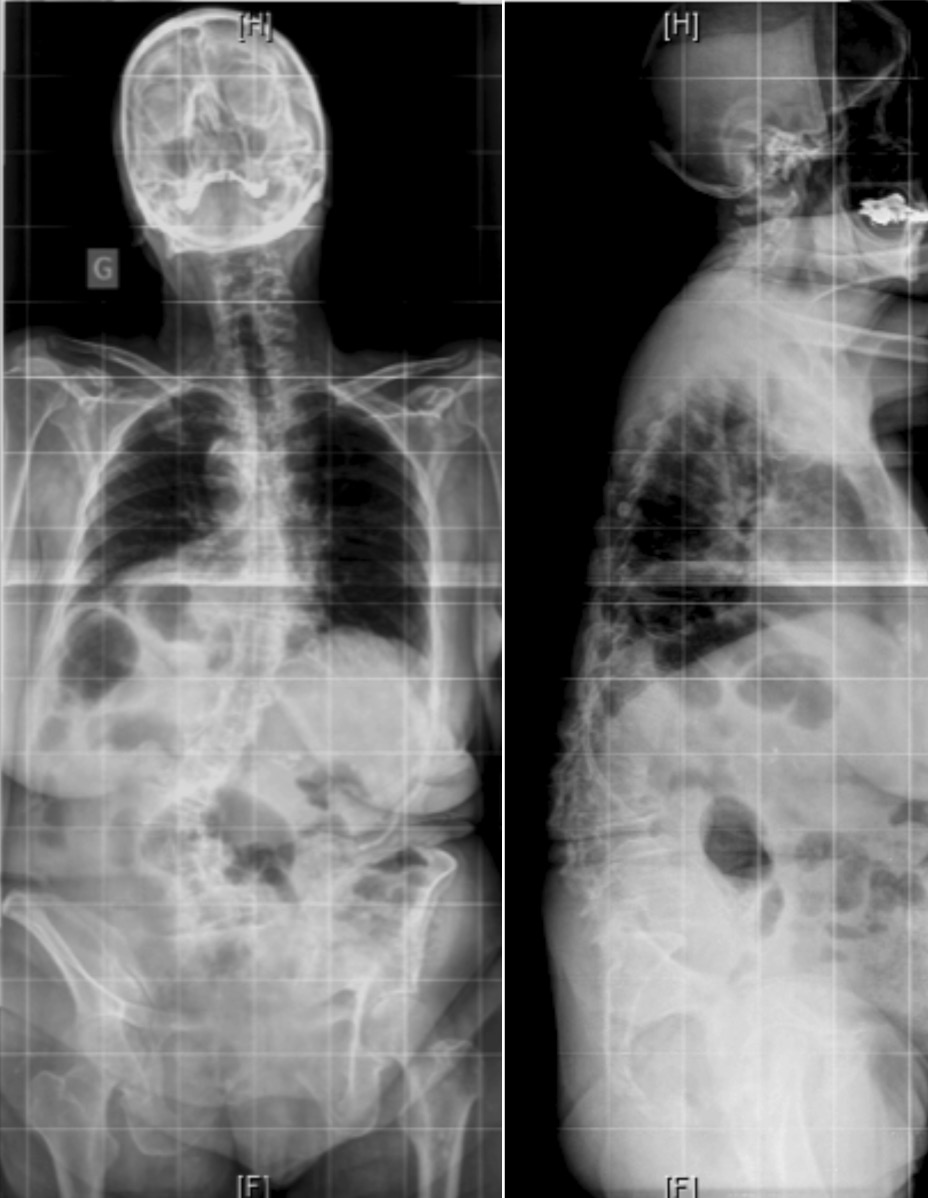

脊柱形态与症状来源

成人脊柱侧凸畸形与后凸畸形

成人脊柱侧凸的腰椎退行性改变也可能会导致椎管或椎间孔的狭窄。超过90%出现神经根疼痛的患者在MRI或CT上出现椎间孔或侧隐窝狭窄,并且通常位于椎间隙出现旋转和半脱位的节段。Gardner等在其文献报道中对侧向半脱位引起的狭窄提出了两种模式:开放性半脱位与闭合性半脱位。在开放性半脱位中,椎间隙在凸侧的张开使椎间盘在对侧突出,这种模式导致对侧(即凹侧)的侧隐窝和椎间孔出现狭窄。 在闭合性半脱位时,椎间盘朝侧向移位侧突出,而导致同侧侧隐窝与椎间孔出现狭窄。笔者认为,充分理解成人脊柱畸形的各种症状的发病机制,将有助于更好的识别成人脊柱畸形患者的症状来源,确认疾病的责任病灶,从疾病根源处解决患者的诉求。尽可能用最小的手术实现最大的症状缓解与功能改善,避免扩大手术范围而破坏脊柱的生理状态,导致翻修手术一而再再而三的发生。

(A)腰椎X线片显示椎体在L1-L2处旋转,椎间盘向凹侧突出,在L2-L3处出现侧向半脱位,椎间盘向凸侧突出;星号表示狭窄部位

(B)轴向MRI显示L2–L3处的凸侧椎间孔狭窄,形成开放性半脱位

(C)L1–L2处的凹侧椎间孔狭窄,形成闭合性半脱位。